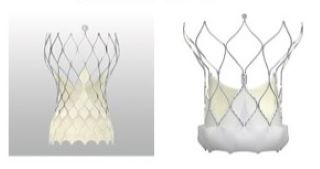

TAVIは、カテーテルに装填された人工弁を、狭窄して機能不全におちいった自己弁の上に拡張し留置します。当院では、風船拡張の手法で留置する人工弁1種類と形状記憶の特性を生かした自己拡張能を有する人工弁の2種類を用いています。鼡径部の大腿動脈から挿入する経大腿動脈アプローチ法、胸の皮膚の小さな切開から心臓の先の心尖部の動きの少ない部位に挿入する経心尖部アプローチ法、他に鎖骨下動脈や胸部大動脈を経由したアプローチ法が、事前にえられた画像情報により、ハートチームにおける検討のもと、適正に選択されます。

TAVIは、カテーテルに装填された人工弁を、狭窄して機能不全におちいった自己弁の上に拡張し留置します。当院では、風船拡張の手法で留置する人工弁1種類と形状記憶の特性を生かした自己拡張能を有する人工弁の2種類を用いています。鼡径部の大腿動脈から挿入する経大腿動脈アプローチ法、胸の皮膚の小さな切開から心臓の先の心尖部の動きの少ない部位に挿入する経心尖部アプローチ法、他に鎖骨下動脈や胸部大動脈を経由したアプローチ法が、事前にえられた画像情報により、ハートチームにおける検討のもと、適正に選択されます。

バルーン拡張型人工弁

自己拡張型人工弁